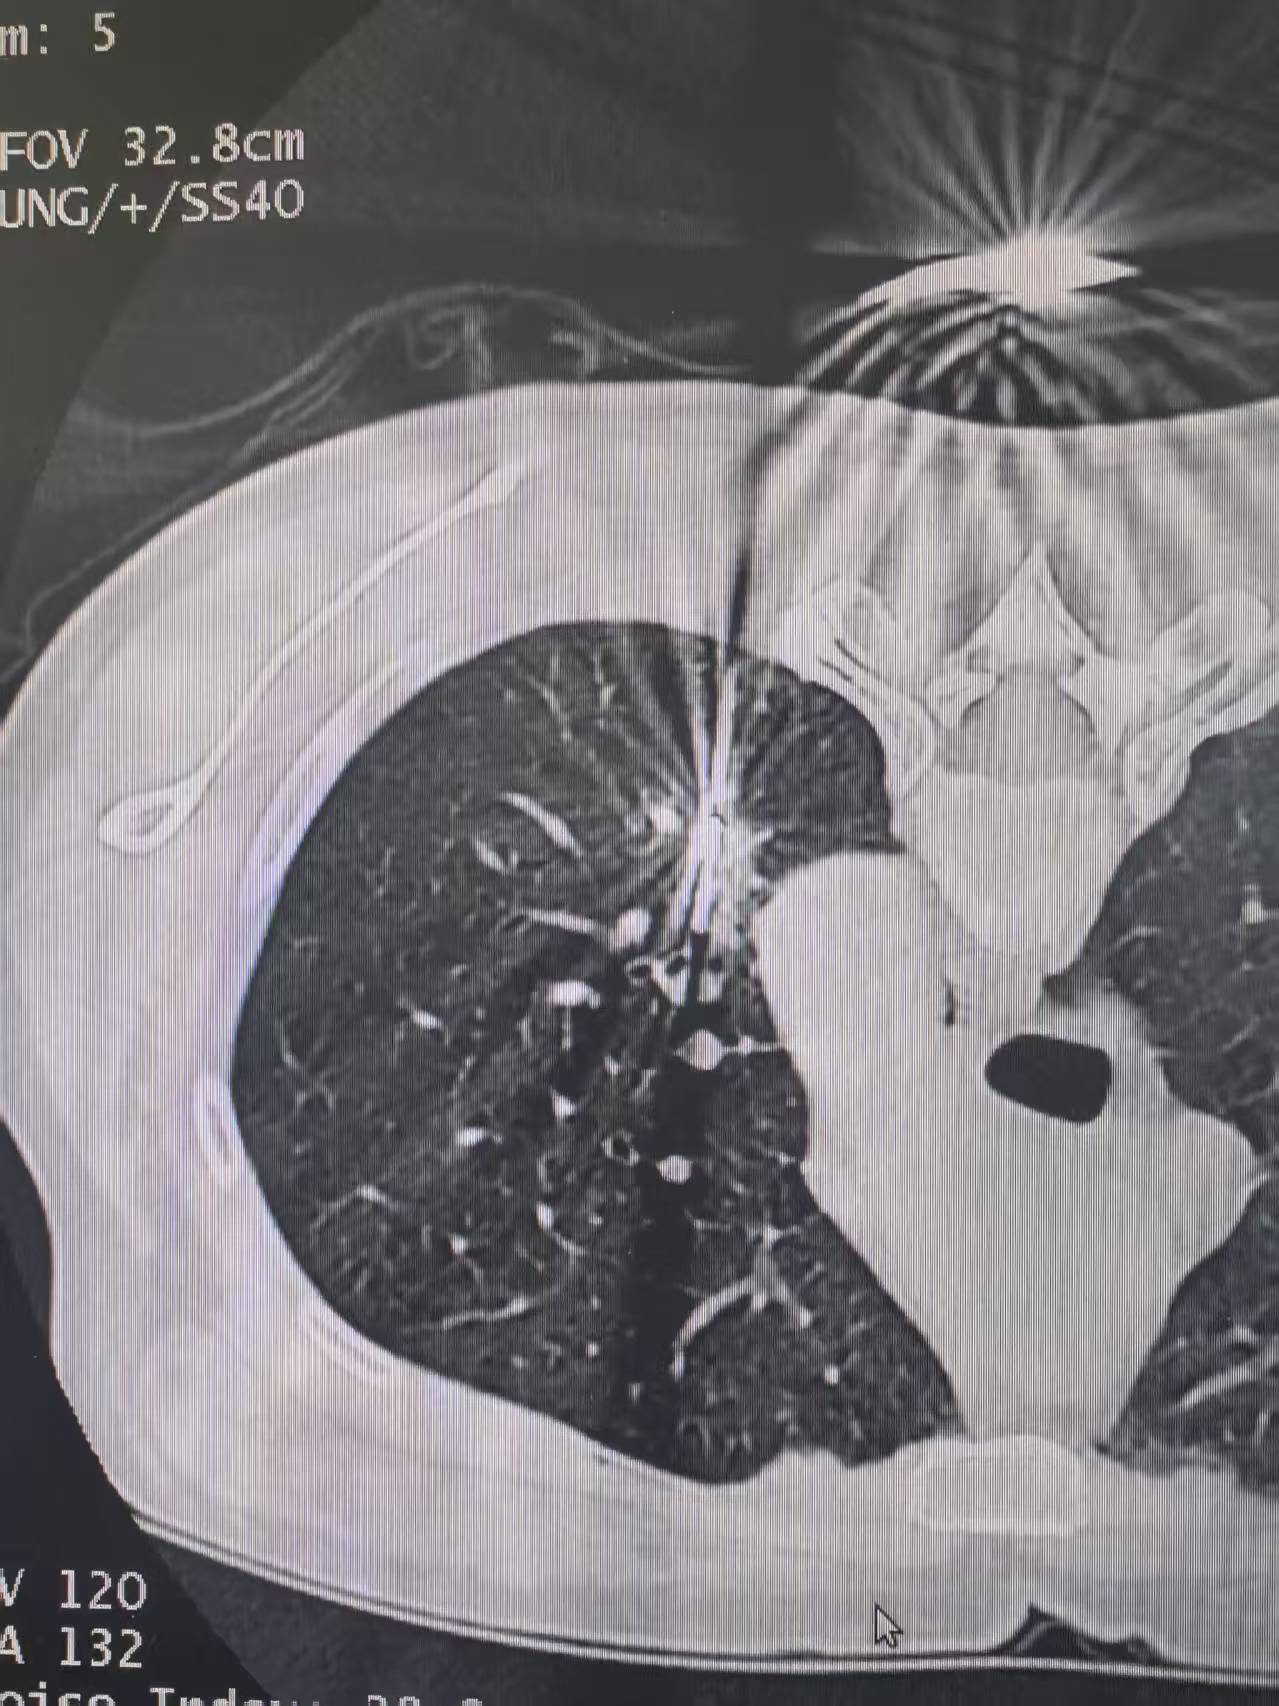

在我的临床随访管理中,长期固定由我们团队跟踪的肺结节患者,已超过2万例。其中,有大量小于5mm的结节,即使我判断可能是肿瘤,也通常不建议立即手术。 1、微小结节的惰性特征 这些结节往往生长极其缓慢,甚至多年不变。许多患者通过线上或线下随访,经长期观察(3年、5年、10年甚至20年),结节几乎没有明显增大。 2、手术代价与获益的权衡 微小结节(如绿豆大小)若位于肺组织深部,手术切除时需连带部分正常肺组织,得不偿失。 过早干预可能影响肺功能,降低生活质量,而观察随访并不会增加风险。 3、“和平共处”策略 对于极早期肿瘤,并非必须“赶尽杀绝”。与其“杀敌一千,自损八百”,不如采取更理性的策略:在确保安全的前提下,保持原装肺结构,维持良好的生活质量。只要结节稳定,长期观察是更优选择。 因此,对于这类微小肺结节,我们更倾向于定期随访而非激进治疗,让患者在不影响生活的前提下,安全监控病情。[玫瑰][谢谢]